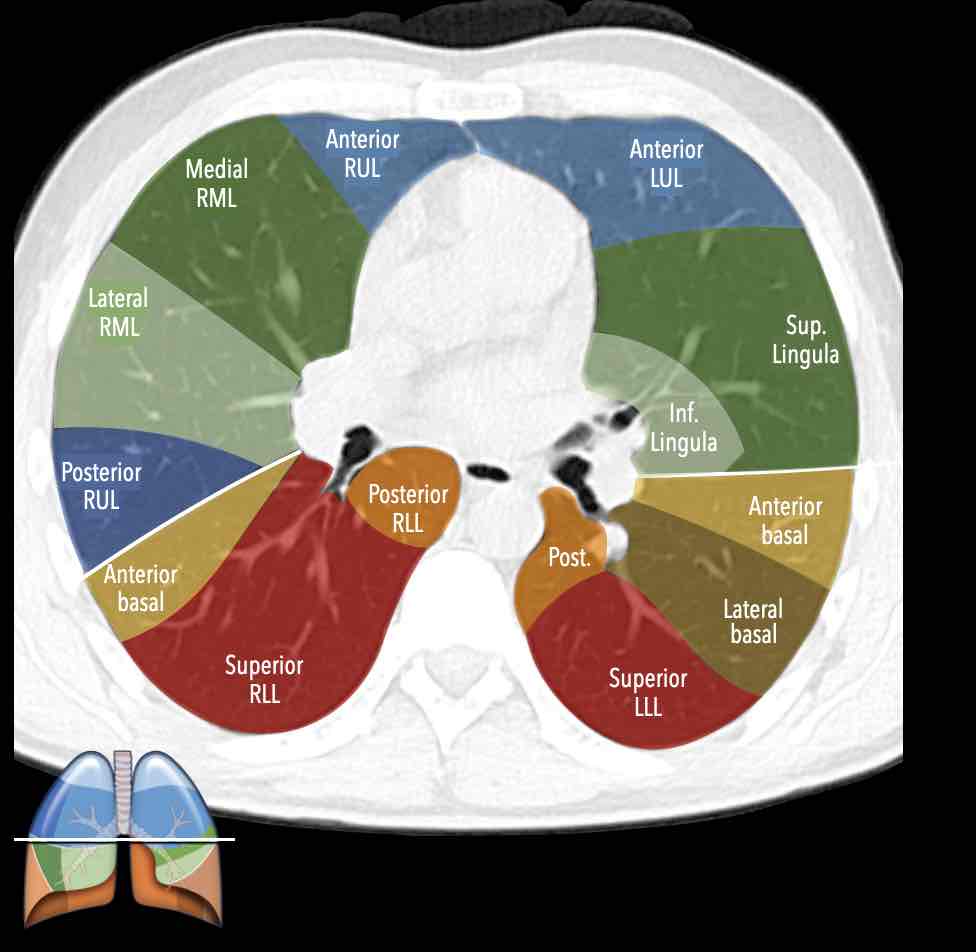

Các phân thùy phổi – hình minh họa

Thùy trên phổi phải (màu xanh lam)

Phân thùy đỉnh (RB1) – Phân thùy sau (RB2) – Phân thùy trước (RB3)

Thùy giữa (màu xanh lá)

Phân thùy bên (RB4) – Phân thùy trong (RB5)

Thùy dưới phổi phải (màu cam)

Phân thùy trên (RB6) – Phân thùy đáy trong (RB7) – Phân thùy đáy trước (RB8) – Phân thùy đáy bên (RB9) – Phân thùy đáy sau (RB10).

Thùy trên phổi trái (màu xanh lam)

Phân thùy đỉnh-sau (LB1/2) – Phân thùy trước (LB3)

Lưỡi phổi (màu xanh lá)

Phân thùy trên (LB4) – Phân thùy dưới (LB5)

Thùy dưới phổi trái (màu cam)

Phân thùy trên (LB6) – Phân thùy đáy trước (LB8) – Phân thùy đáy bên (LB9) – Phân thùy đáy sau (LB10).

Danh sách tất cả các phân thùy phổi. Trong ngoặc là số thứ tự theo phân loại Boyden, thường được các phẫu thuật viên và bác sĩ hô hấp sử dụng. Lưu ý rằng phân thùy 7 không có ở phổi trái.

Giải phẫu phân thùy của hai phổi có tính đối xứng nhất định, vì phổi trái chỉ khác phổi phải một chút.

Phổi phải có ba thùy (gồm thùy trên, thùy giữa và thùy dưới) với mười phân thùy,

trong khi phổi trái có hai thùy (gồm thùy trên và thùy dưới) với số phân thùy ít hơn.